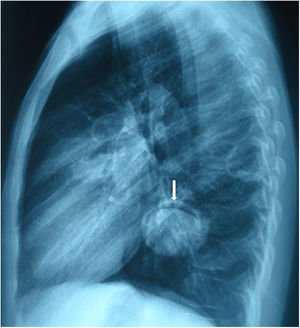

A 17 years old male presented with cough. Posteroanterior and lateraly direct radiography showed cavitary lesion in the middle zone and “moonsign” in the lower zone of the right lung (Figs. 1 and 2). The patient underwent right thoracotomy. Cystotomy and capitonnage was performed to hydatid cyst.

Fig. 2.

Moon sign is seen on the lateral chest X-ray (arrow).

Radiologically, there are many radiological signs associated with the hydatid cyst.1,2 Moon sign is seen when air enters between the pericyst and endocyst. This finding indicates that the hydatid cyst will rupture. Radiological findings have an important role in the diagnosis of pulmonary hydatid cyst.